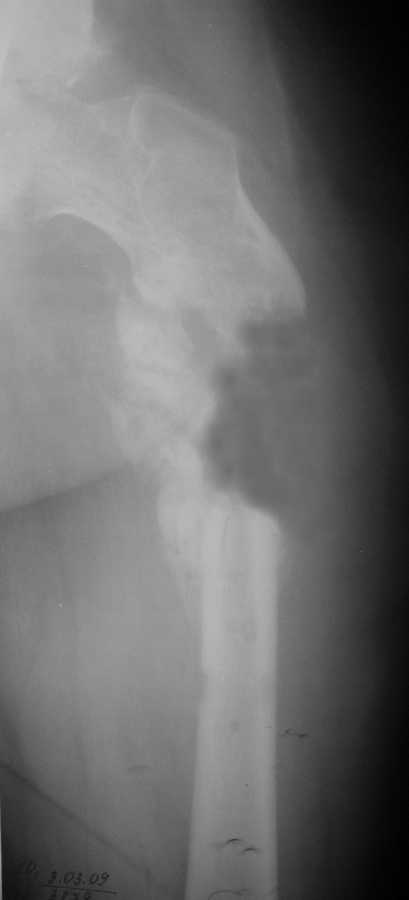

Уважаемые коллеги, у пациента 26 лет имеется дефект в\з бедренной кости образовавшийся в результате СНЭ по поводу травматического остеомиелита

Также имеется травматическая деформация таза с трансвертлужным переломом на стороне дефекта. Планируется замещение дефекта транспортом кости.Хотелось бы услышать ваши советы по поводу оптимальной компоновки АВФ (стержневой, спице-стержневой), есть ли необходимость в дополнительной фиксации за кости таза?

сделать закрытый интрамедуллярный остеосинтез. В дефекте есть признаки костеобразования, так что вполне ожидаемо сращение.

А вот таз - отдельная проблема, вернее, две - краниальное смещение правой половины таза, и нелеченный высокий поперечный перелом вертлужной впадины. Как Вы намереваетесь решать эти проблемы?

Хотел-бы поддержать точку зрения уважаемого А.Н. Челнокова - больших проблем с бедром тут не должно быть, ситуация с тазом куда более серьезная. Судя по крестцово-подвздошному, там более 5 см смещение.

Нужды в транспорте кости аппаратом не видно, потому что это не сегментарный, а краевой дефект, и такие дефекты можно закрыть дополнением аутокостью из крыла.

Насчет таза там большие упущения, пластина на симфизе - доказательство отсутствия знания методики лечения переломов таза и ацетабулум. Хотя бы скелетным вытяжением можно было приблизить правую половину таза.

Разрыв крестцово-подвздошного сочленения и поперечный перелом вертлужной впадины являются показанием для оперативного лечения.

4. Дефект бедра сегментарный - в ходе операции удалён фрагмент бедренной кости до 7 см.